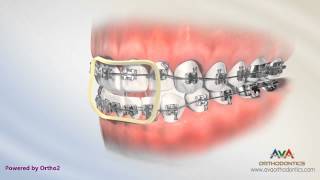

Orthodontic Treatment for Openbite Rubber Bands video

Orthodontic Treatment for Openbite - Rubber Bands

Orthodontic Treatment for Openbite - Rubber Bands How to Wear Rubber Bands - Vertical or Triangle Upper 3 Lower 3, 4

How to Wear Rubber Bands - Vertical or Triangle Upper 3 Lower 3, 4 Anterior Openbite (bite block)

Anterior Openbite (bite block) Orthodontic Treatment for Overjet (Overbite) - Rubber Bands

Orthodontic Treatment for Openbite - Rubber Bands

Orthodontic Treatment for Openbite - Rubber Bands How to Wear Rubber Bands - Vertical or Triangle Upper 3 Lower 3, 4

How to Wear Rubber Bands - Vertical or Triangle Upper 3 Lower 3, 4 Anterior Openbite (bite block)

Anterior Openbite (bite block) Orthodontic Treatment for Overjet (Overbite) - Rubber Bands